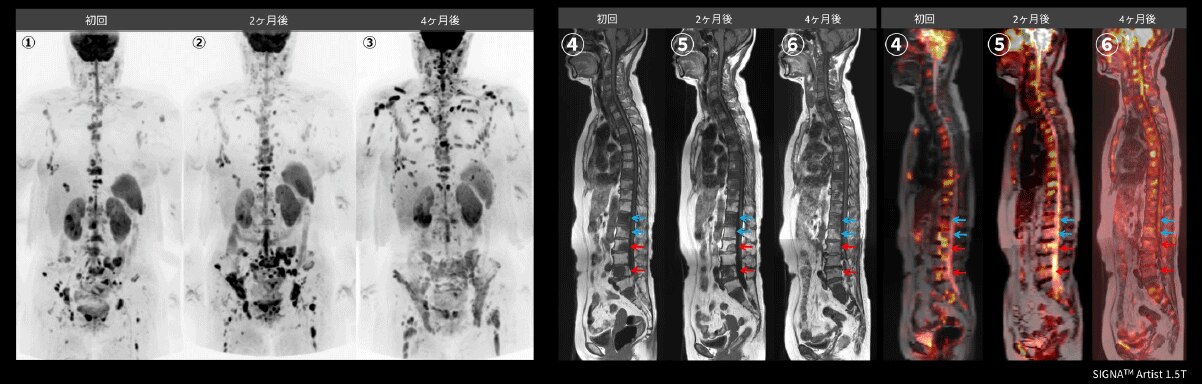

Case3 呼吸器内科:肺癌の骨転移検索目的

70代、男性。肺癌に対して放射線化学療法後、腰痛出現するも単純CTでは原因を特定できず、WBDWIを施行した。WBDWI MIP(①)では、頸椎、胸椎、腰椎、鎖骨、骨盤骨、大腿骨など多発骨転移と肝転移も認められる。②~④の矢状断像では、WBDWI MIP(①)で椎体に重なっていた棘突起の転移、CT(⑤⑨)では描出困難な腰椎、仙骨、腸骨転移(➞)がMRI(⑦⑩)では明瞭に描出されている。まさに骨梁間型骨転移の典型例である。単純CTでは描出されていない肝転移(➞)においてもDWI(⑦)、T2WI(⑧)では明瞭に描出されている(図12)。依頼医からは肺癌は骨梁間型骨転移が多く認められるため、肺癌の骨転移検索にWBDWIは非常に有用であると評価が得られた。

図12 肺癌の骨転移検索目的